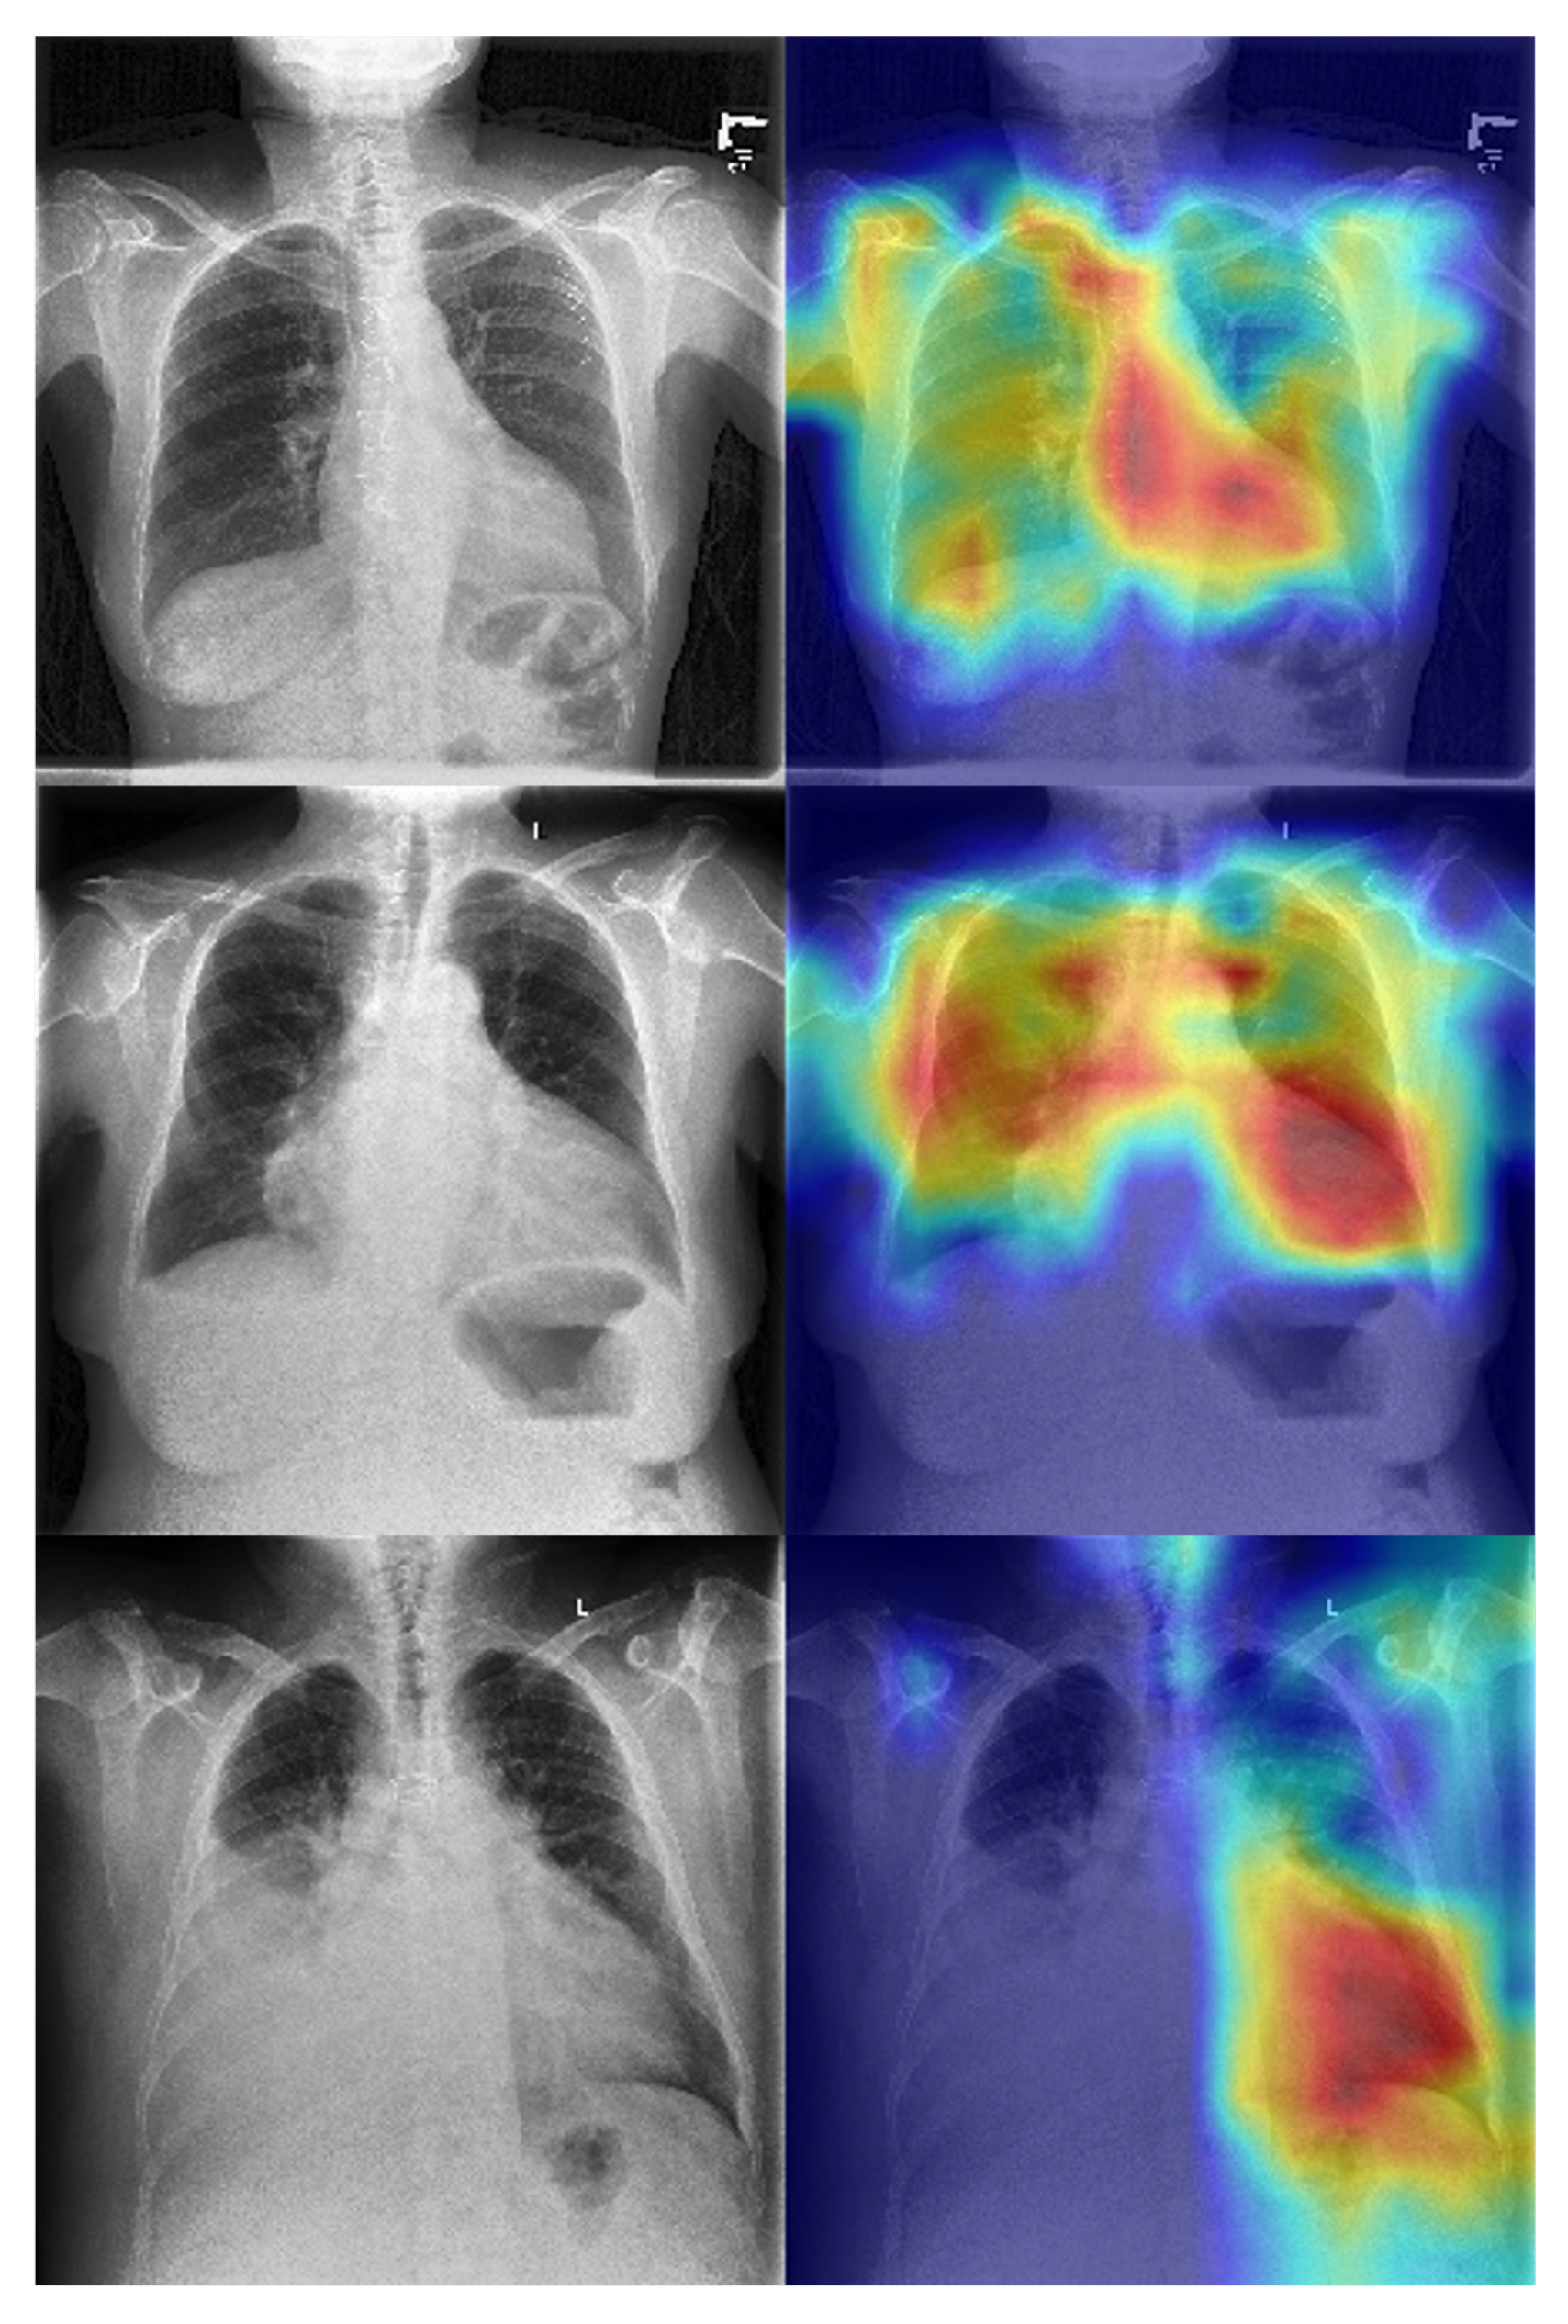

The superior performance of the ViT model is likely driven by its global self-attention mechanism, which enables modeling of long-range anatomical dependencies across the thoracic cavity, a capability that convolutional architectures lack due to their reliance on localized receptive fields. These findings establish that SLVH-relevant cues are sufficiently encoded in chest radiographs to support high-accuracy direct classification when leveraging appropriate architectural priors and pretraining strategies. We show some exemplar GRADCAMs here to further strengthen the interpretability of model decisions in Figure 5. Across multiple examples, we observe that the model consistently attends to central cardiac regions, particularly the mediastinum and left ventricular silhouette, with high-intensity activations (red regions). This localization aligns with the expected anatomical correlate of severe left ventricular hypertrophy, where cardiac enlargement and changes in ventricular wall thickness manifest most prominently in these areas. Importantly, the activations are concentrated around the cardiac contour rather than diffuse pulmonary fields or image borders, suggesting that the network is not relying on spurious features such as rib patterns, background artifacts, or acquisition markers. These interpretability results reinforce the clinical plausibility of the learned features and provide additional transparency. They suggest that the model’s predictions are informed by relevant cardiothoracic structures, in agreement with radiological and cardiological understanding of hypertrophy, thereby increasing confidence in its potential utility.

Figure 5.

Grad- CAM activation maps for enhanced interpretability on our ViT backbone.